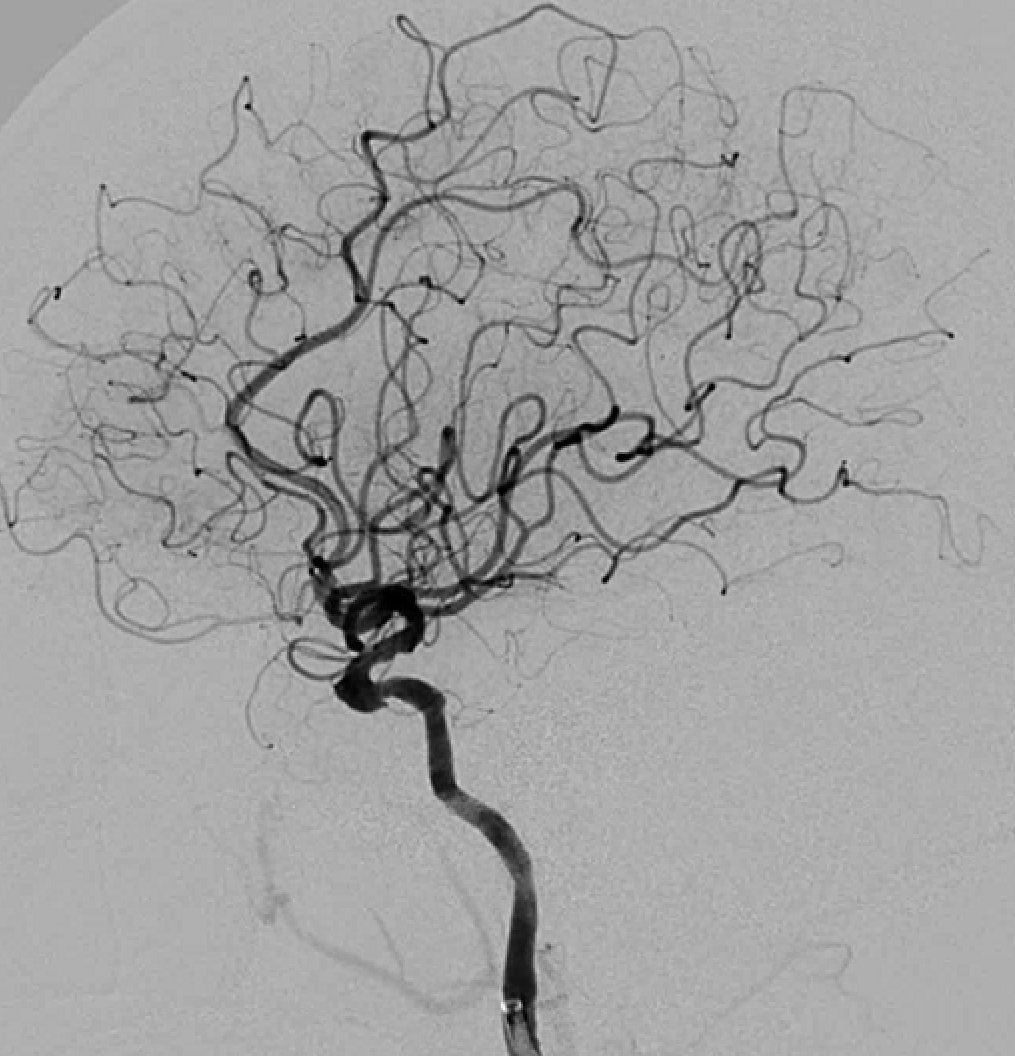

右侧颈动脉造影

左侧颈动脉造影

手术过程

左侧瘤体形态欠规则,4mm×30mm Streamline 优先处理左侧动脉瘤

术后3月复查,瘤体未见显影,载瘤动脉通畅

同期4mm×20mm Streamline 进一步处理右侧动脉瘤